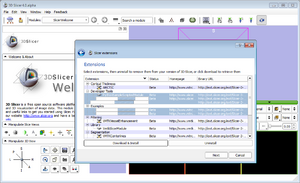

Slicer

Modules

Dialogs